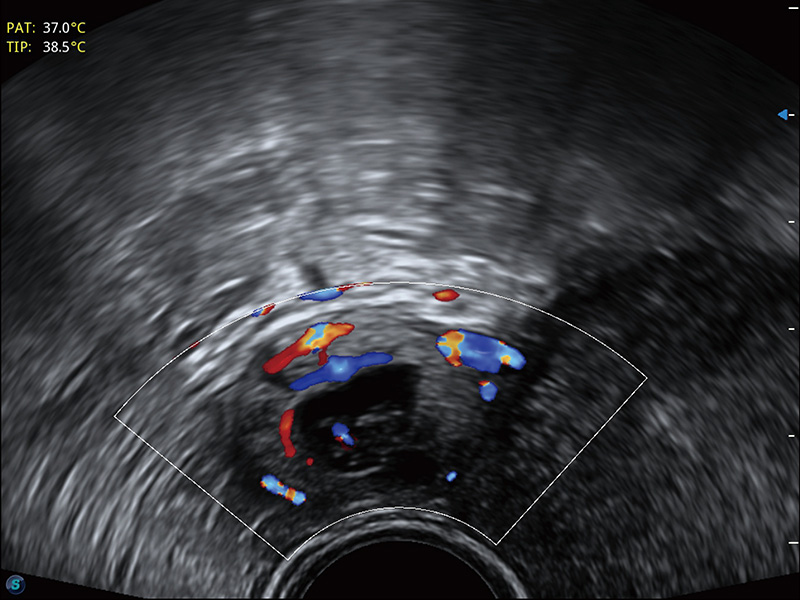

“生育问题”即关系民族复兴,也关系亿万家庭的幸福。随着婚育年龄推迟、社会压力增加等因素,越来越多人群也面临着“生不出、生不好”的问题。辅助生殖作为治疗不孕不育最有效的方法之一,也逐渐成为育儿新希望。而超声检查能为生殖需求人群的初诊评估提供宝贵的信息。 P20 Elite是球速体育入口匠心打造的一款生殖应用型彩超。她继承球速体育入口高端极光平台,突破性地将多款新型芯片及硬件模块进行整合,均衡了高端系统性能与小巧灵动机身。P20 Elite卓越的图像质量搭载专科探头,旨在为您提供全面的辅助生殖解决方案。

P20 Elite配备了丰富的生殖探头群和临床应用功能,在卵泡监测、穿刺取卵、胚胎移植、妊娠确认等领域,为生殖需求人群提供了新的临床机会,重新定义高端超声如何应用于生殖健康检查。

耦合剂加热器可将耦合剂维持在舒适的温度,体现患者关爱。